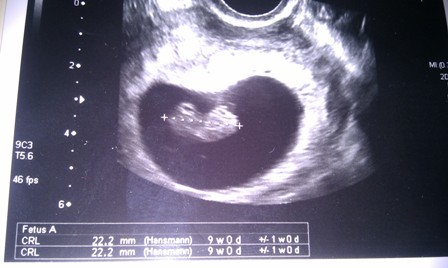

śliczności :-)WitajcieWróciliśmy do domku. Sytuacja już opanowana- plamienia ustały i wszystko ma się dobrze. Biorę 2razy2 luteinki dowcipnie i no-spe i liczę na to,że już będzie dobrze. Dziś miałam robione USG

Rozumiem ze wszystko OK.............................?:-):-)